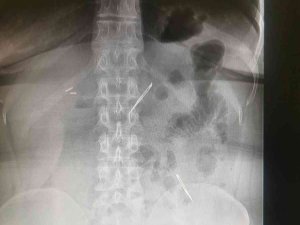

Karın Ağrısı Şikayetiyle Gitti, 2 Tane Neşter Yuttuğunu Öğrendi